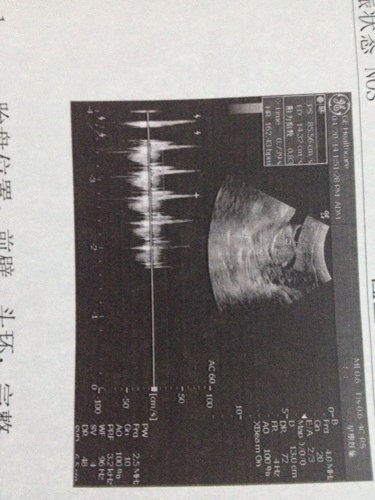

三个多月了BB,能不能看男女,BPD2.58cm PL1.45cm 胎心162次/分 胎盘 前壁!

三个多月了BB,能不能看男女,BPD2.58cm PL1.45cm 胎心162次/分 胎盘 前壁!我想要女儿!知道的谢谢了!

病情分析: 这个胎心太高了,要看是有什么异常导致的,要等大一些的时候,直接做彩超看情况的。 指导意见: 同时也可以多做几次看胎心,如果一直都是比较高的,那么女孩子的机会大一些的。